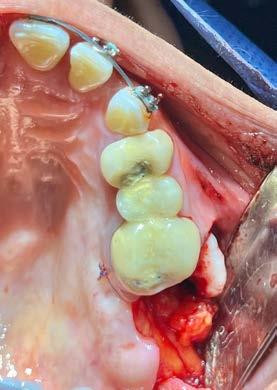

Por lo que se propone procedimiento quirúrgico con la evidente comunicación oroantral al realizar las extracciones de los órganos dentales involucrados. Previa asepsia y antisepsia, colocación de campos estériles, extracción de segundo y tercer molar superior derecho e incisión envolvente con descarga mesial (Figura 3), rotación y afronte mediante puntos simples de la bola adiposa de Bichat para el cierre de la comunicación oroantral (Figura 4), farmacoterapia con base en amoxicilina con ácido clavulánico. Una semana después refiere no presentar rinorrea y mejoría al 100% de la obstrucción. Posterior a 6 meses de evolución clínica (Figura 5) y radiográficamente (Figura 6), no se observa comunicación oroantral o paso de líquidos de la cavidad oral a la cavidad nasal.

4. Cierre de comunicación con la bola adiposa de Bichat.